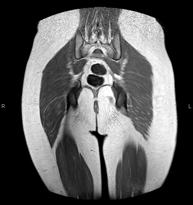

- Hip MRI

Examination for the study of injuries to tendons, muscles and hip joints. Enables early detection of hip osteoarthritis. It is very useful for detecting bursitis and dynamic osteopathy of the pubis, which is common in athletes. It lasts approximately 20 minutes. It is a radiation-free procedure.

- Gluteal MRI

Examination to study the muscles and tendons that originate at this level, such as the hamstring tendons, which are frequently injured in athletes. It lasts approximately 16 minutes. It is a radiation-free procedure.